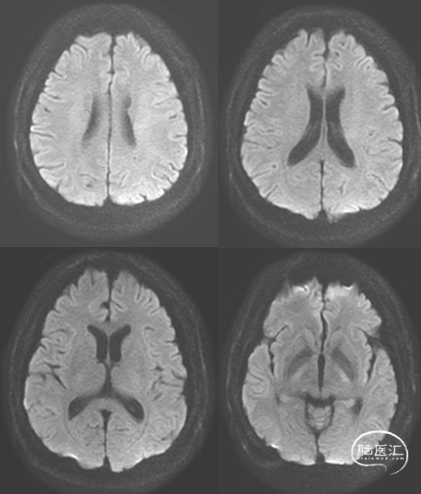

头颅核磁DWI未见急性梗死,T2加权像见双侧增粗眼静脉。